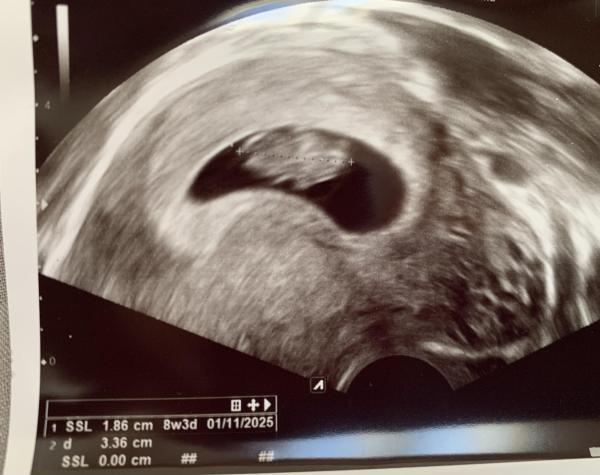

Hallo zusammen,  So wie es aussieht fahre ich das zweite Mal mit im November-Bus!    Bei meinem Sohn war ich im Nov 23 schonmal ungeplant mit dabei, jetzt bin ich wieder ungeplant schwanger. Nach dem ersten Schock über die (erneute) Unzuverlässigkeit von Verhütungsmitteln behalten wir es wahrscheinlich, steht aber noch nicht 100% fest...  beim 1. US hieß es ET 03.11. beim 2. US ET 01.11. soweit verläuft also Alles bestens, Herzchen schlägt usw.  anbei ein erstes Foto vom Würmchen,  Granantapfel, 25 Jahre mit 💙🧒🏼 16 Monate

Bild zu Wahrscheinlich auch mit dabei - Forum für November - Mamis